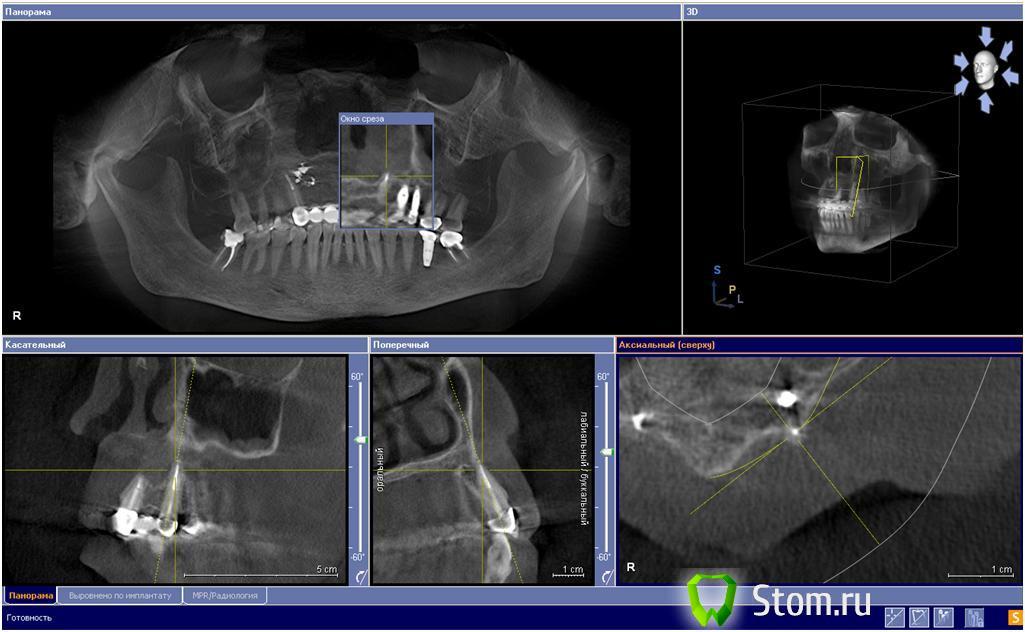

FBR Опубликовано 9 декабря, 2011 Поделиться Опубликовано 9 декабря, 2011 (изменено) Доброго времени суток коллеги. Пациентка обратилась пол года назад с жалобой на периодичекое припухание в области верхней губы и болевые ощущения в проекции верхушки 23 возникающие с периодичностью 1-2 раза в месяц (локализация определена пальпаторно) . 23 на момент обращения интактный. 22 и 24 отсутствуют более 10 лет. На КТ определяется выступающаяя верхушка корня 23. У меня на данный момент есть желание резецировать верхушку корня, т.к. считаю что причина периостальной реакции из-за нее. Хотелось бы услышать ваше мнение коллеги. Заранее спасибо. Изменено 9 декабря, 2011 пользователем FBR Ссылка на комментарий

kriokov Опубликовано 9 декабря, 2011 Поделиться Опубликовано 9 декабря, 2011 (изменено) 23 , канал пломбирован, Вы наверное оговорились насчет интактногоНа аксиальном срезе "фонит" что-то постериальней верхушки 23, ,(там не избыток материала за клыком?) на других срезах вроде этого не видно, и на сагиттальном за верхушкой 23 на деструкцию похожеимхо, на ревизию сходил бы, приготовился бы на крайняк для ретроградного, еще бы лору показать, чтоб в носу посмотрел Изменено 9 декабря, 2011 пользователем kriokov Ссылка на комментарий

kriokov Опубликовано 9 декабря, 2011 Поделиться Опубликовано 9 декабря, 2011 может стоит просто сделать хорошее эндо ортоградно... Не уверен. Смущает тень выделенная желтой стрелкой на аксиальном срезе, на избыток пломбировочного похоже. Красная- тень верхушки 23 с пломбировочным, сразу под надкостницей. Ссылка на комментарий

FBR Опубликовано 30 декабря, 2011 Автор Поделиться Опубликовано 30 декабря, 2011 Коллеги. большое спасибо за участие. Пациентка прооперирована. проведена РВК 23 с ревизией очага за ним. Удалено большое количество пломбировочного материала. В области ревизии ( сразу за верхушкой) интраоперационно, обнаружена полость примерно 10 мм, без оболочки, такое ощущение что кость просто под действием материала лизировалась. Сегодня 4 день после операции, отек проходит , синячок, жалоб на боли не предъявляет. Контрольные снимки выложу после нового года. Всех с наступающим!!! Ссылка на комментарий